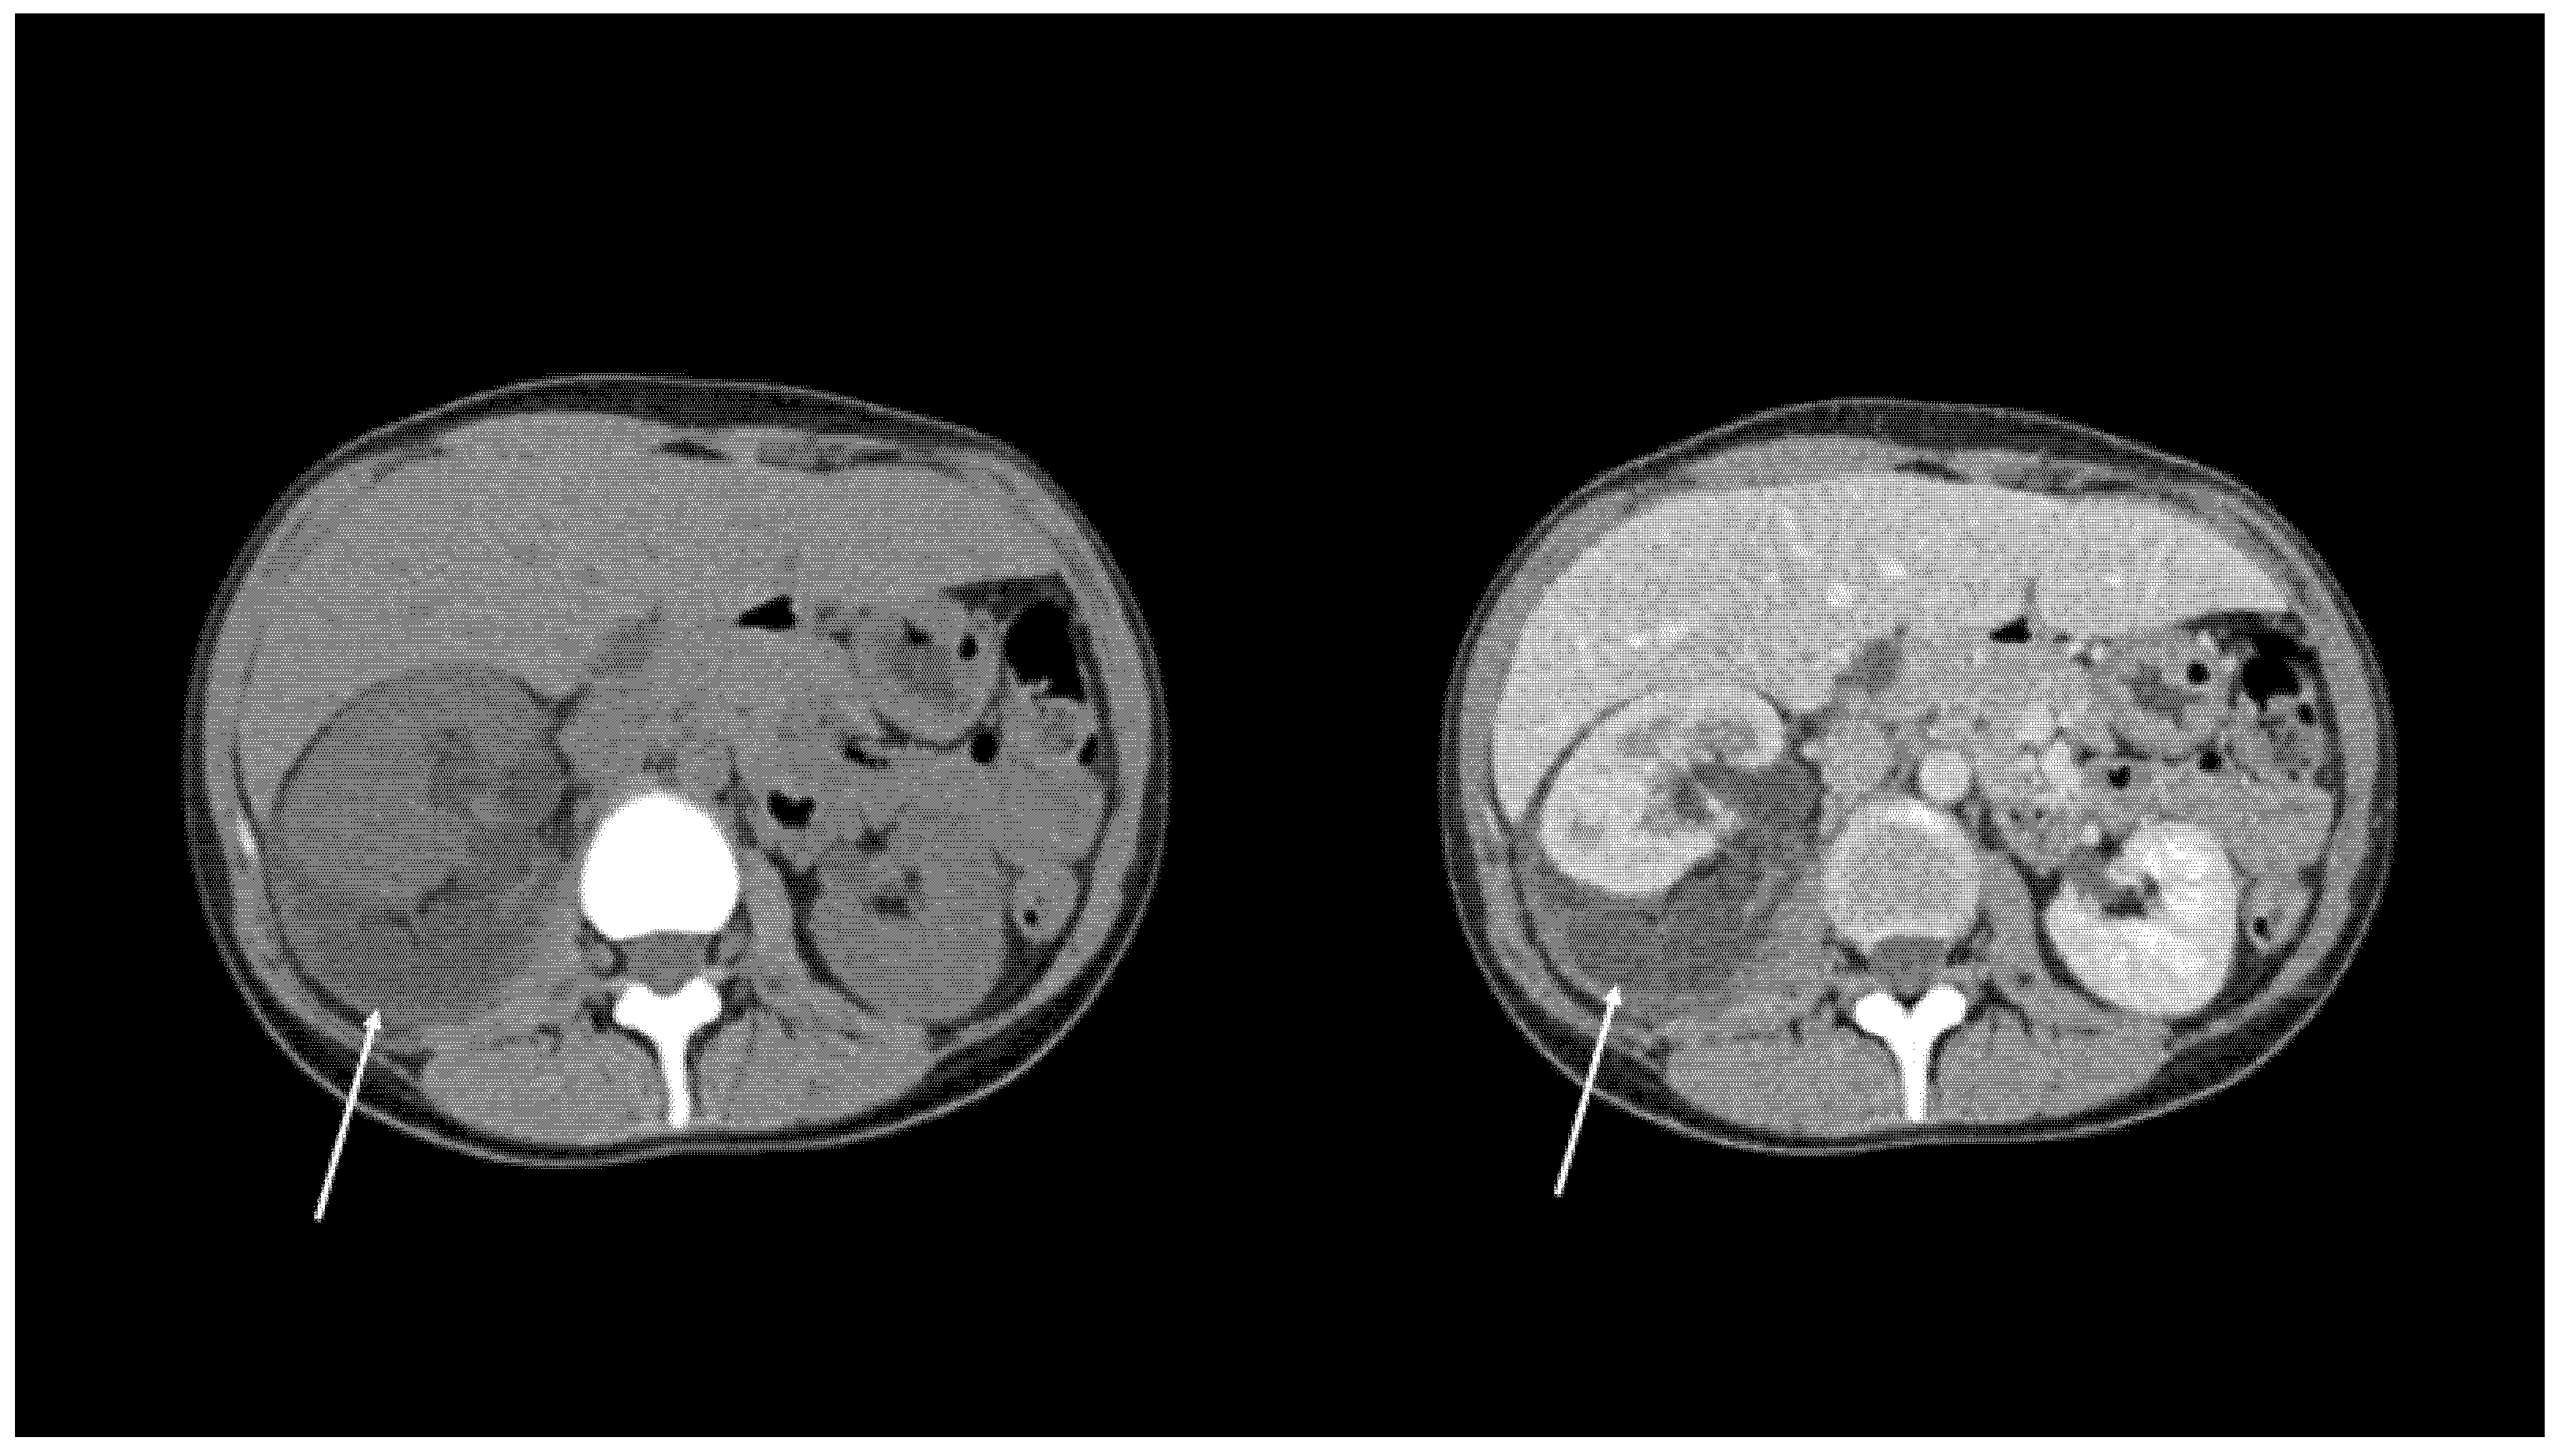

| Local spread | 24 (36.4%) | 27 (40.9%) | 26 (39.4%) |

| Free Fluid | 39 (59.1%) | 36 (54.5%) | 35 (53.0%) |

| Urinoma | 3 (4.5%) | 3 (4.5%) | 5 (7.6%) |

| Cohen’s Kappa | 0.74 * | 0.72 *; 0,70 § | |

| ICC (95% CI) | 0.88 (0.81–0.93) * | 0.87 (0.79–0.92) *; 0.86 (0.78–0.92) § |